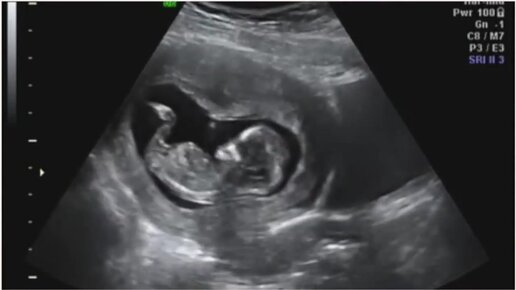

УЗИ на 12 неделе беременности